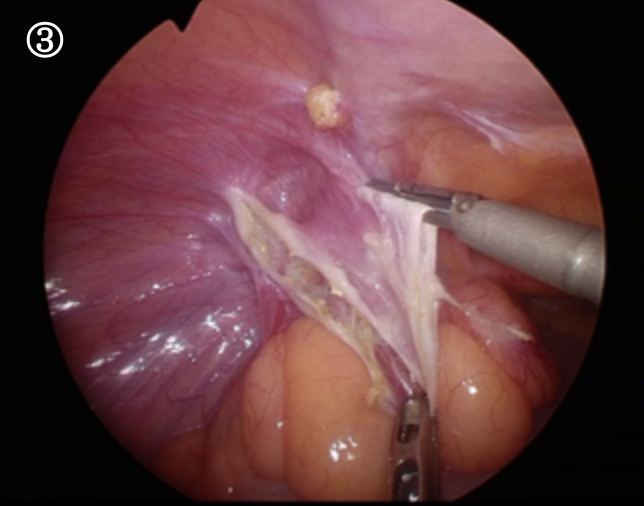

ぽっかりと大きなトンネルが見えます。これがヘルニア門と言われる穴です。腸の一部はこの門の奥に癒着し、完全には引き出すことが出来ませんでした

このヘルニア門に沿って腹膜という薄い膜を切っていきます。